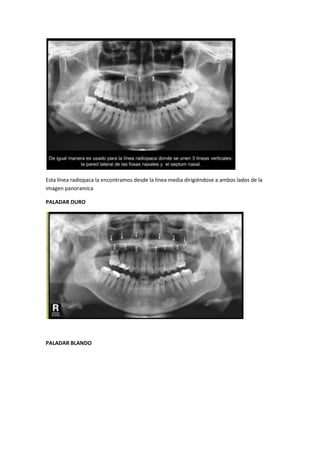

Esta línea radiopaca la encontramos desde la línea media dirigiéndose a ambos lados de la

imagen panoramica

PALADAR DURO

PALADAR BLANDO